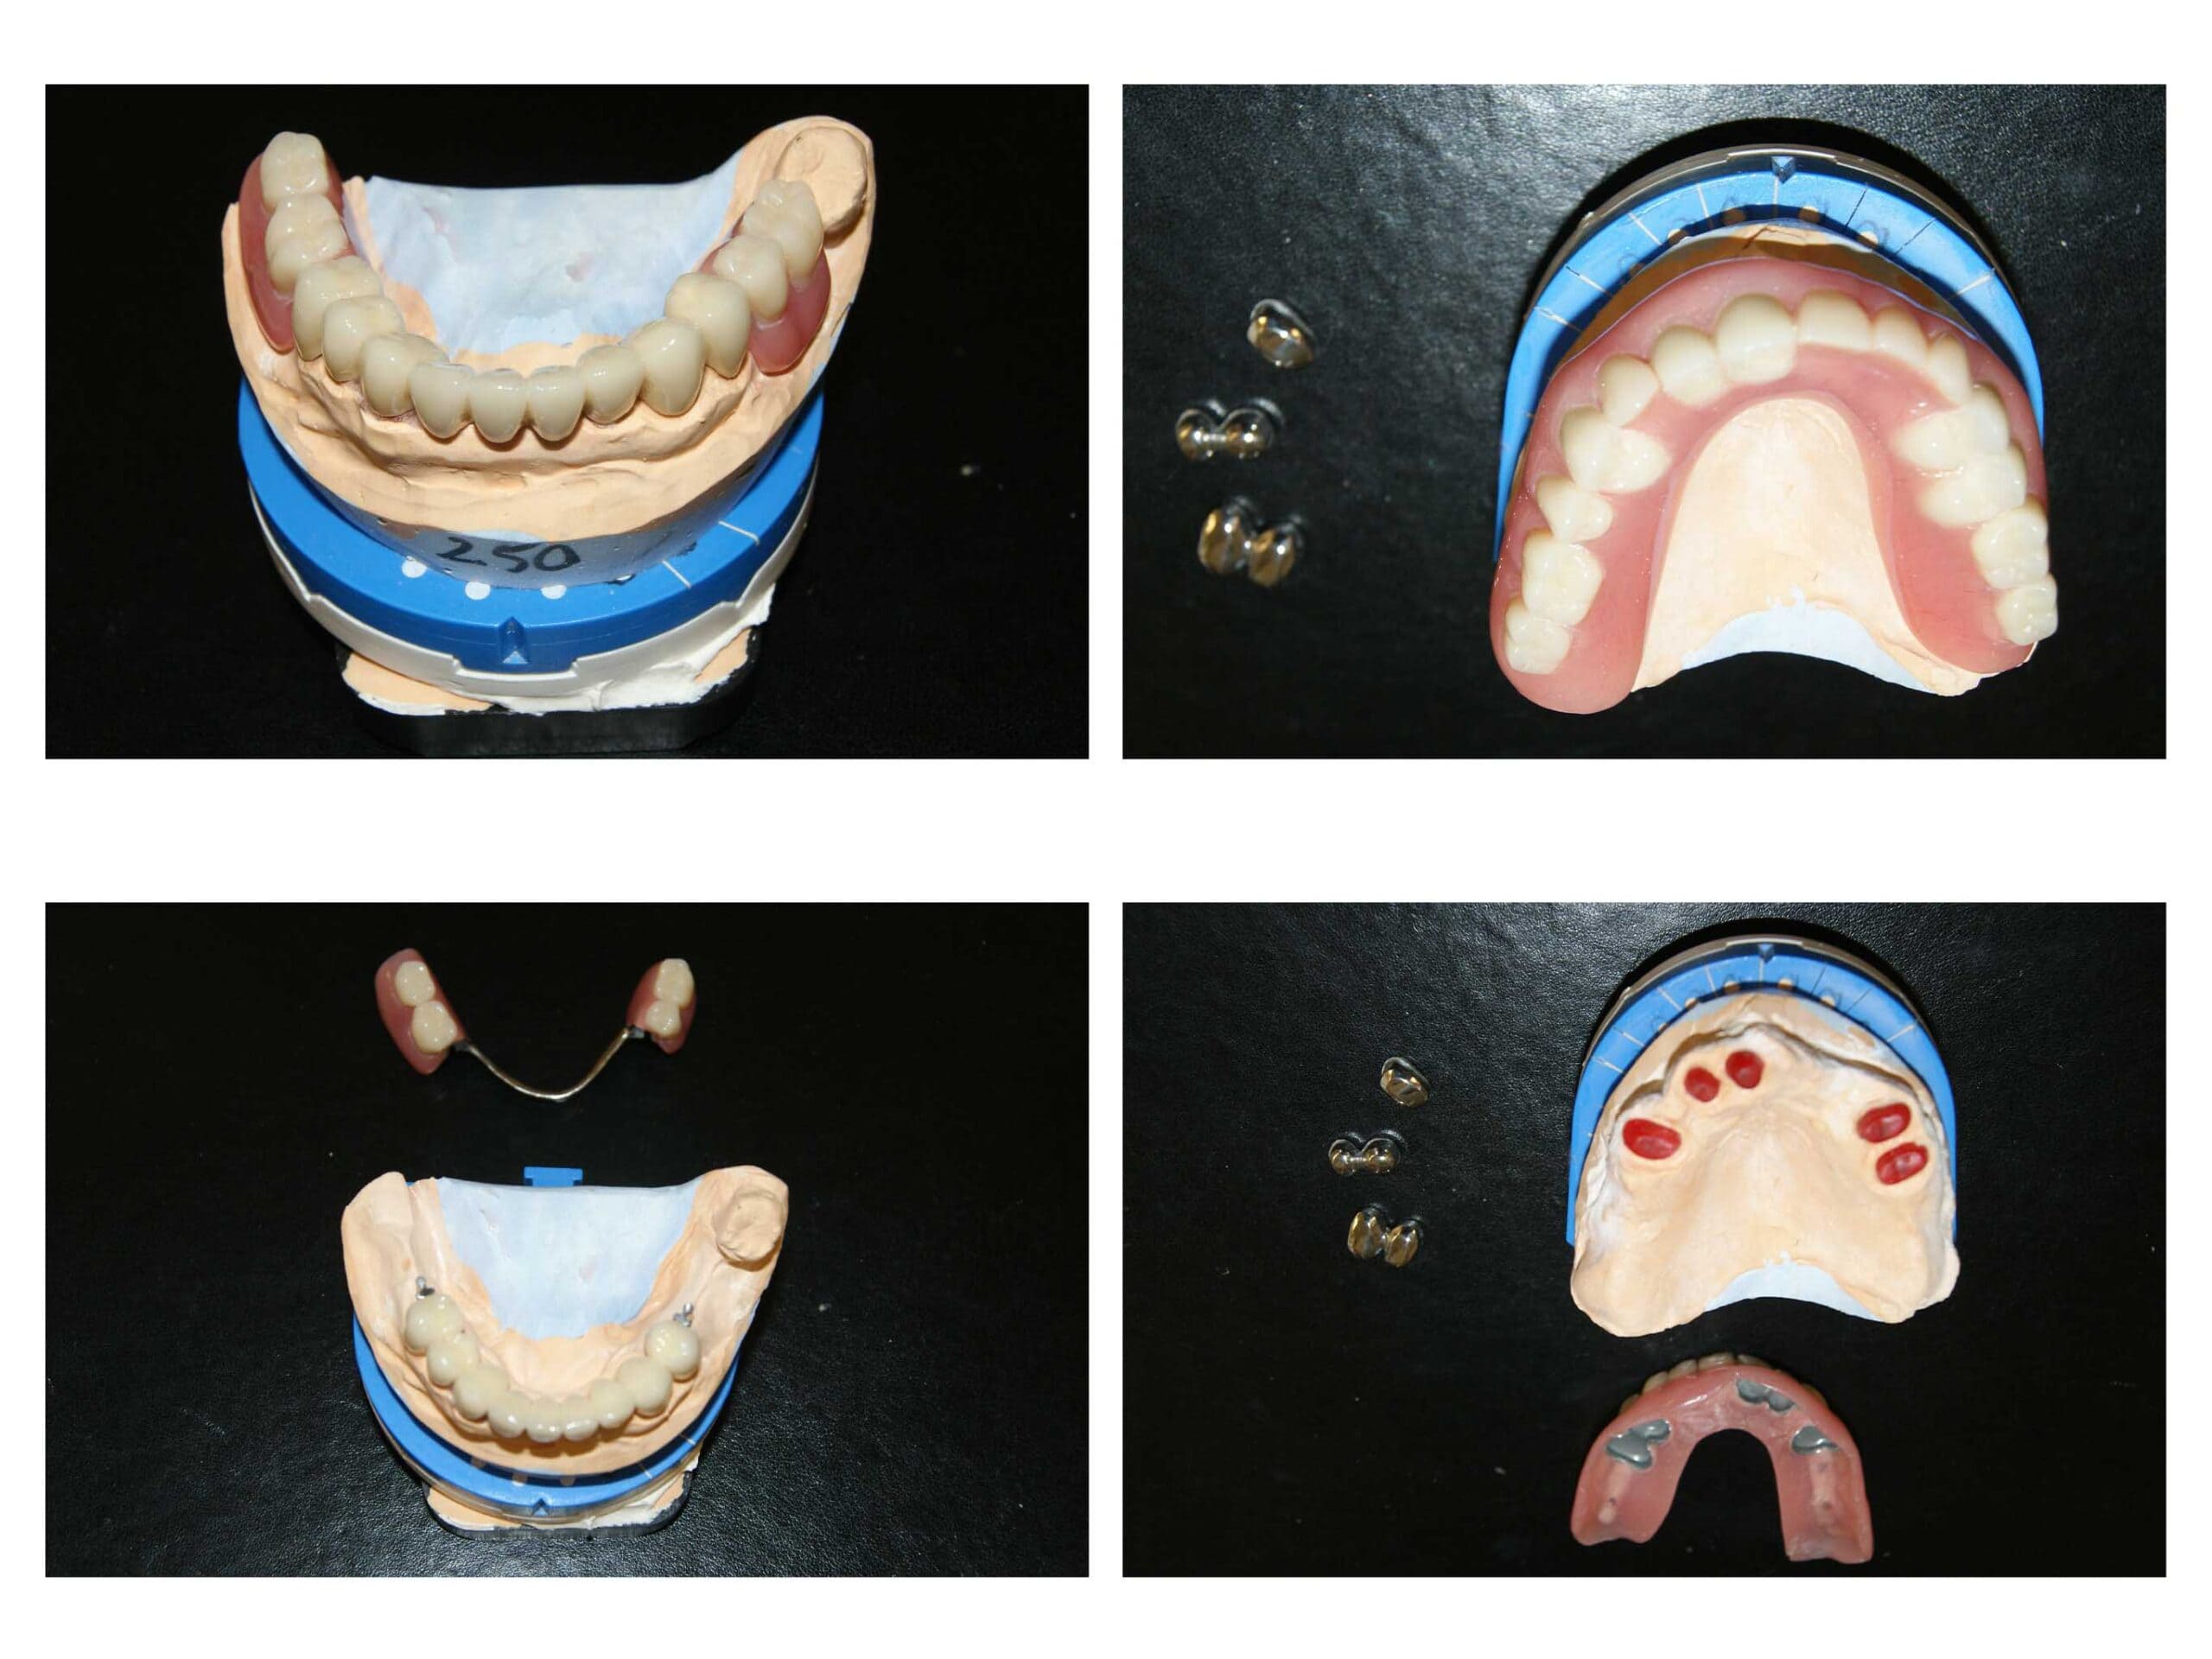

Proteza telescopată  și proteză scheletată aplicate pe dinții tratați corect! Execuția riguroasă oferă stabilitate excelentă.

Lucrare fixată pe dinți împreună cu proteză scheletată mobilizabilă = soluția de lux pentru dinți puțini